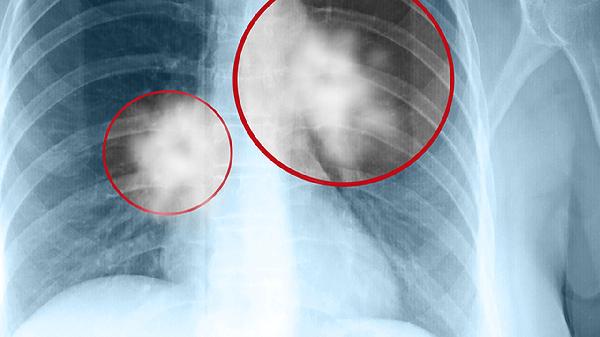

維護肺部健康需建立長期健康習慣,每日保證充足水分攝入,睡眠時間不少于7小時。出現(xiàn)持續(xù)咳嗽、胸悶等癥狀時應(yīng)及時進行胸部CT檢查。特殊職業(yè)人群建議每年進行肺功能篩查,居家可定期監(jiān)測血氧飽和度。冬季注意保暖防寒,避免呼吸道感染誘發(fā)肺部疾病。